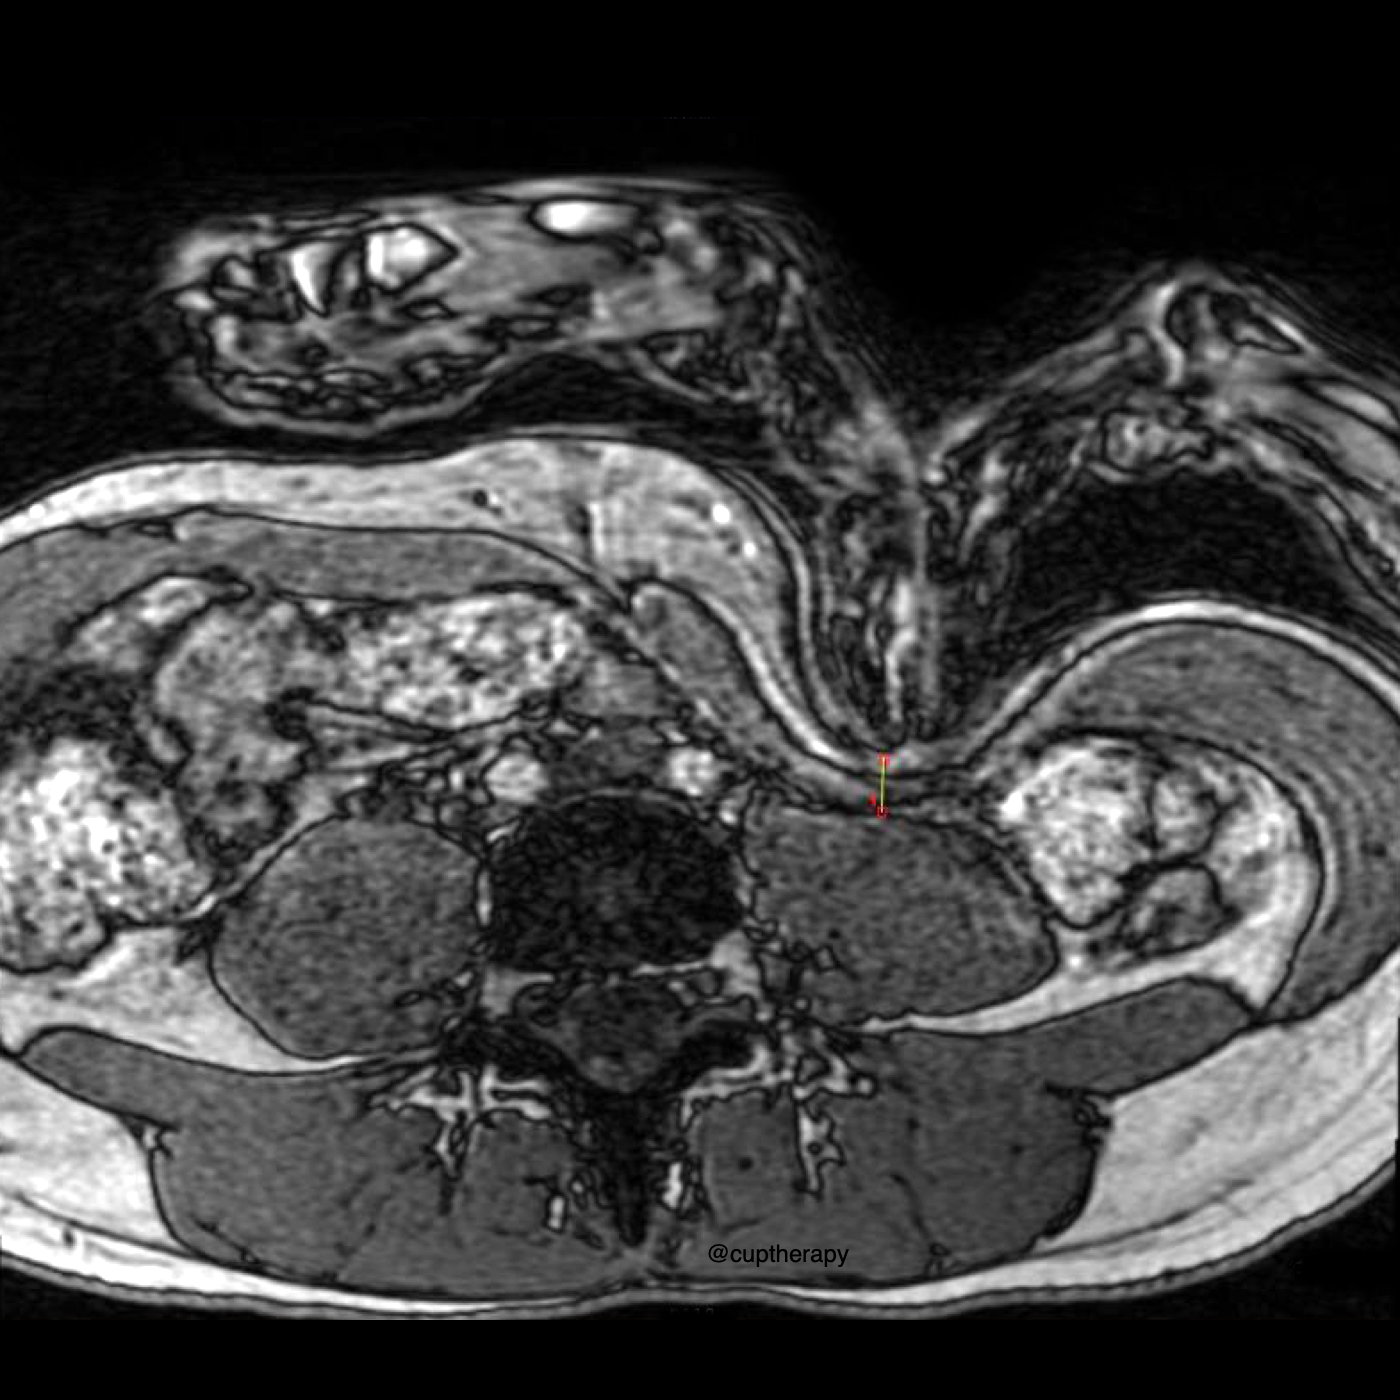

Can manual therapists actually palpate the psoas, or is it anatomically out of reach? In this episode, Til Luchau and Whitney Lowe unpack a new real-time MRI pilot study presented at the 7th International Fascia Research Congress by UCSF physical therapist Christopher DaPrato and colleagues. The study offers rare imaging-based insight into what really happens when we try to touch this deep, controversial muscle. And at the end, Christopher drops in for a brief bonus segment to share safety insights and his hopes for future research.

– How DaPrato’s team used dynamic MRI to observe what happens under the hands during attempted psoas palpation

– What the images showed about depth, tissue layers, and muscle deformation when pressure is applied

– The surprising finding that even a higher-BMI participant showed clear psoas shape change under palpation

– How viscera behaved under pressure — including what the study suggests about visceral compression and safety

👉 Episode image courtesy Christopher DaPrato @cuptherapy

No, I don’t recall that. If you did, I don’t recall it. That’s, but you’re right. It is really deep there. It’s behind a lot of the viscera, yeah. And it’s, it’s, you know, very far down lower down in the abdominal bowl there. Yeah, I’ll go ahead and share one of those headline findings, the palpation with both the hands and the tool. And both subjects reached to within seven to 11 millimeters of the psoas. That’s like less than half an inch in both cases. So we could see the actual tissues getting displaced, and this the tip of the subject’s fingers, or the tool itself within seven millimeters, sometimes of the psoas. Yeah.

Yeah, right, yeah. Okay, so, so if it’s not touching, if it’s seven millimeters away, does that mean that there’s still other stuff in between where it appeared, the fingers were with the MRI, and the actual muscle itself, if it was not directly making contact, like, are you, is that still, like, internal, abdominal organs, or, you know what, what’s what’s in that gap in that what’s

in that gap? Yeah, well, there’s skin, there’s abdominal wall, and there’d be some the fascia covering of the psoas. But I think the presumption was the viscera had moved out of the way. He had some clear comments about this, but in his view, because, because one of the critiques of working this was, is you got to poke through viscera, and viscera right soft, so it was displacing, but not he said it in alarming ways. There was some compression against the psoas, but not pushed aside dangerously and not being pinned in ways that he considered dangerous about the image. I mean, seven millimeters is pretty thin. I mean, if we just look at 7 to 11 millimeters, that’s we’re right. There we are literally as close as you could get to the psoas and, yeah, instances. And again, his takeaway was that no that there’s all kinds of visceral movement anyway, normally, and including in normal postural changes or leaning

Yeah, interesting. I think also in there, he mentioned something about shape changes with the iliopsoas that were, was that the result of the pressure being applied in that region there? Or what was it? What were the shape changes?

That’s significant, because the question, Can we touch it as one thing, but are we actually influencing it as another? And at least again, the MRI is going to show shape. And so the MRIs did show a shape change. You can see the size deflecting around the point of contact in a way. So we’re we are actually moving or changing its shape, rather causing it to deflect or bend around the point of contact.